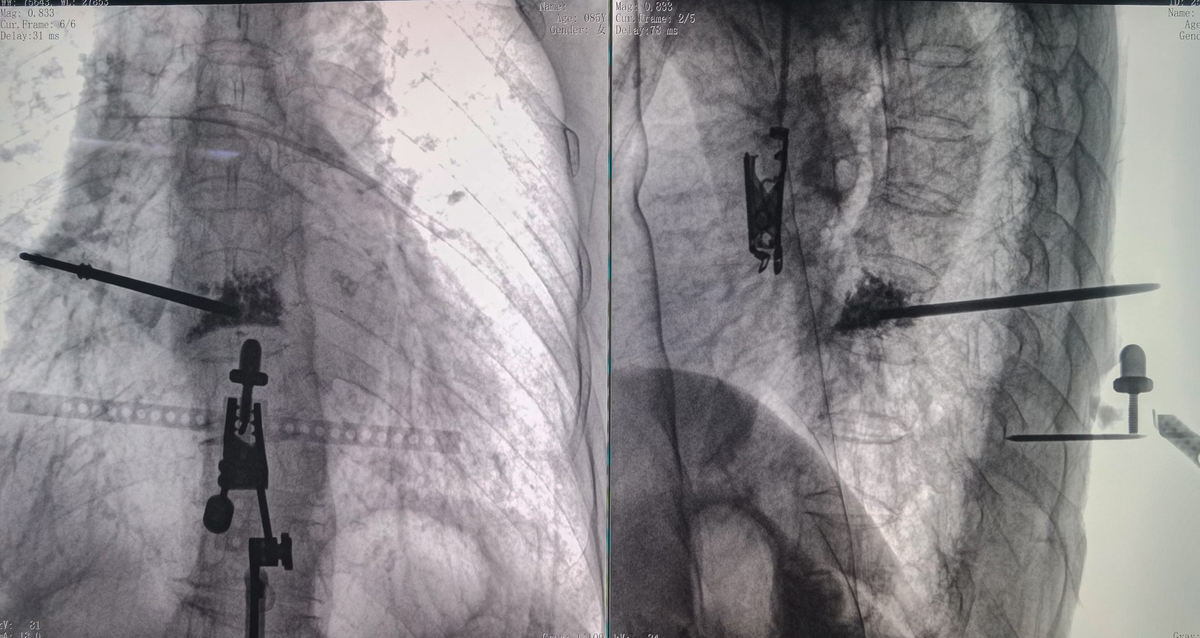

Хирурги могут заранее спланировать оптимальную траекторию пункции на рабочей станции робота, используя трёхмерные реконструкции, полученные с помощью C‑дуги. Затем роботизированная рука направляет и стабилизирует ход операции, обеспечивая однократное точное введение инструмента и формирование рабочего канала, минимизируя повреждение хрупкой костной ткани и снижая риск вторичных переломов или коллапса задней стенки позвонка. Во время введения костного цемента хирург может точно контролировать скорость и объём инъекции, сочетая интраоперационную визуализацию и мониторинг в реальном времени, что позволяет эффективно укрепить позвонок и одновременно строго соблюдать безопасные пределы, предотвращая утечку цемента.

5. Клинические случаи

5.1 Случай 1: пациентка 87 лет

Пациентка имела в анамнезе множественные компрессионные переломы позвонков на фоне тяжёлого остеопороза. Повторные переломы привели к деформации и искажению анатомии позвонков, что существенно повысило требования к точности пункции. Кроме того, наличие сердечно‑лёгочных сопутствующих заболеваний ограничивало интраоперационную переносимость и дополнительно усложняло проведение вмешательства.

5.2 Случай 2: пациентка 83 лет

Пациентка ранее перенесла операцию на поясничном отделе позвоночника и имела хронические переломы грудных и поясничных позвонков, а также рёбер, что привело к выраженному разрушению тел позвонков и окружающих анатомических структур и значительному повышению хрупкости костей. Во время операции пункция сопровождалась высоким риском вторичных переломов, а распространение костного цемента было трудно точно прогнозировать. Дополнительно у пациентки имелись сопутствующие заболевания, включая сахарный диабет 2 типа, хронический гастрит и жировую дистрофию печени, что обусловливало низкую общую физиологическую переносимость и предъявляло строгие требования к точности и эффективности хирургического вмешательства.

5.3 Случай 3: пациентка 85 лет